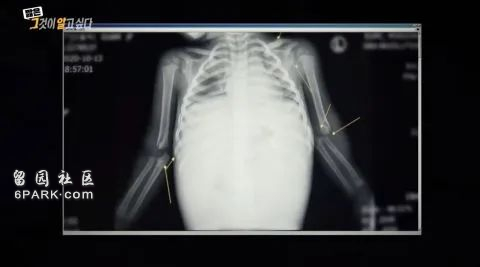

离开的时候,郑仁全身都是瘀血,内脏破裂,头部、肋骨、手臂、腿部多处骨折。腹部内积满血,甚至连胰腺也出现破裂,像一个支离破碎的布娃娃。抢救室医生愤怒发声:“这完全可以作为教科书上虐待儿童的示意图”。

试问,胰腺破裂会在什么情况下出现?胰腺破裂,相当于交通事故中受到猛烈撞击的剧烈强度;也同样是一个成人从沙发上重重跳下,才会导致1岁的孩子胰腺破裂。